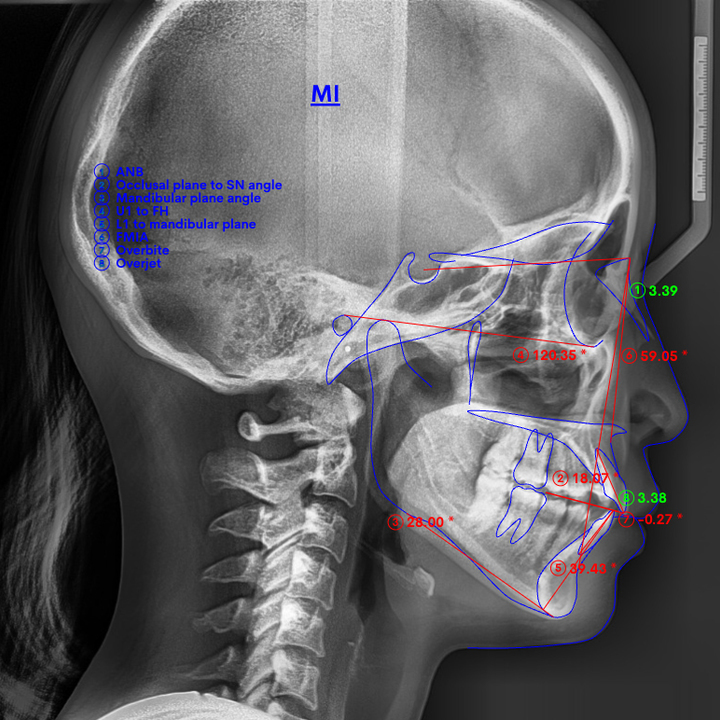

上下顎前突(じょうげがくぜんとつ)とも呼ばれる口ゴボは、上下の前歯が前方に飛び出して見える症状。

口ゴボを矯正すると、前方に飛び出した唇の位置が下がり、横顔のシルエット(Eライン)がすっきりと整います。当院のマウスピース矯正(インビザライン)で、こうした変化を実現可能です。

口ゴボの矯正治療にはいくつかの方法がありますが、治療法によって前歯を引っ込められる量が異なることをご存知でしょうか。

前歯だけの矯正で引っ込められるのは、実は3mm限界です。

あなたの口ゴボは、3mmで治りますか?

では、口ゴボを改善するにはどれくらい引っ込めればいいのか。横顔の変化を実感できるのは、最低でも前歯が4〜5mm引っ込んだとき。重度の口ゴボなら、7〜8mmは必要です。